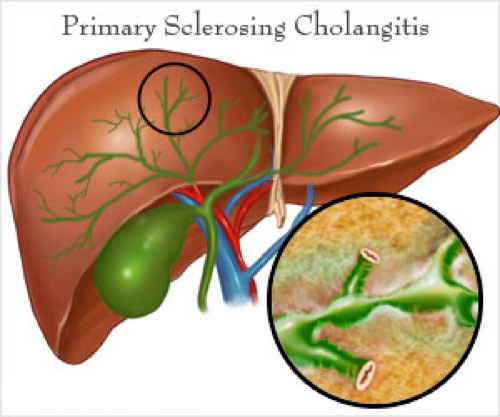

Фотографии и изображения, связанные с симптомами первичного склерозирующего холангита